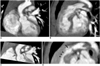

Fig. 13

Right ventricle CT volumetry in 8-year-old boy with repaired tetralogy of Fallot. Retrospective ECG-gated spiral CT was performed because of inconsistent right ventricle volumes on serial cardiac MR examinations (end-systolic volume of right ventricle was normalized to body surface area, 86 → 128 ml/m2).

A. Crisp margin of right ventricle is shown with high spatial resolution on volume-rendered CT image.

B, C. Consequently, right ventricular cavity can be accurately segmented with three-dimensional region growing method. End-systolic volume of right ventricle that's normalized to body surface area calculated with CT is 86 ml/m2, which indicates that volume at second cardiac MR examination is inaccurate.